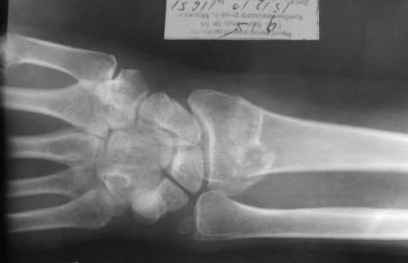

Уважаемые коллеги.Прошу обсудить случай лечения перелома дистального метаэпифиза

лучевой кости. Ситуация скандальная и крайне неблагоприятная.

15.12- перелом луча в Москве. Там же репозиция, гипс. Дальнейшее

лечение у нас в ЦРБ. 20.12.- вторичное смещение в гипсе

21.12- под внутривенным наркозом - репозиция, гипсовая лонгета.

рентгенологов и консультанта из КДЦ областной больницы- стояние отломков допустимое.

Объективно говоря- снижена высота лучевой кости, диастаз лучелоктевого сочленения, и не

сросся шиловидный отросток. однако на РКТ при сравнении с другой стороной- разница

незначительная.

1.Прошу объективно оценить качество нашей репозиции на момент 21.12. (неужели так плохо?).

Что на снимках при снятии гипса- сам вижу.

2. сравнить снимки РКТ (с двух сторон)- так ли велико укорочение лучевой

кости и лучелоктевой диастаз.